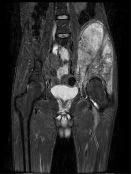

Kıkırdak hücresi üreten kötü huylu bir tümördür. En sık 30-60 yaş arasında görülür. Sıklıkla femurun (uyluk kemiği) her iki ucunda, humerusun (kol kemiği) üst ucunda, pelvis (leğen kemiği), kaburga, omurga ve kafa kemiklerinde görülebilir. Kondrosarkomlar primer ve sekonder olmak üzere iki gruba ayrılır. Elde nadir görülmesine karşın malign el tümörleri içerisinde üst sıradadır.

1. Klasik Medüller Kondrosarkom

Sıklıkla pelvis (leğen kemiği), femurun (uyluk kemiği) ve humerusun (kol kemiğinin) üst ucunu tutar. Kondrosarkomların %80’nini oluşturur. 30 yaş üzerinde sık görülür. Grade I kondrosarkomlarda lezyon içerisine girilerek geniş küretaj yapılır. Grade II ve üzeri lezyonlarda lezyon için cerrahi girişimlerde lokal nüks riski çok yüksektir. Bu tip kondrosarkomlarda mutlaka geniş sınırlar ile rezeksiyon yapılmalıdır. Histolojik derece çok yüksek ise kemoterapi eklenebilir.